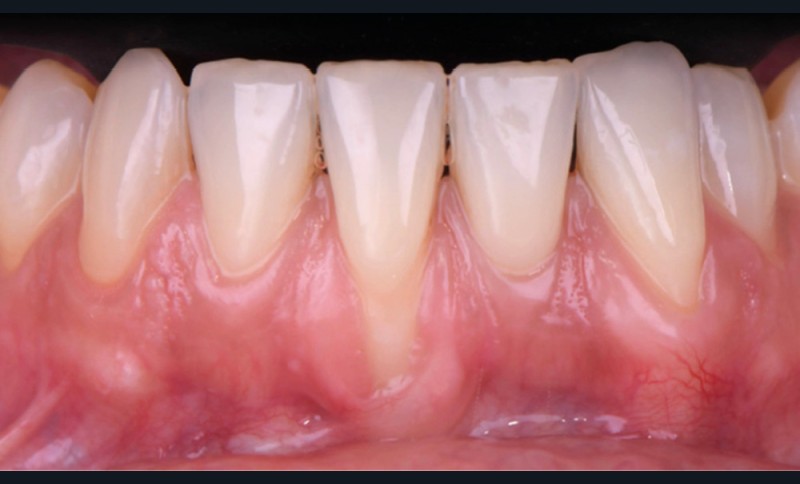

La greffe gingivale libre

La réussite de la greffe gingivale libre passe par l’analyse et la maîtrise de critères liés à la technique chirurgicale, au praticien et au patient. Parmi ces critères, il convient d’évaluer si la situation préo–pératoire présente des risques, notamment en évaluant l’épaisseur des berges du futur lit receveur, ainsi que la quantité de racine à recouvrir. L’absence de prise en compte de ces éléments peut potentiellement conduire à une erreur thérapeutique.

Plus généralement, le stress lié à l’expérience du praticien et celui dégagé par le patient doivent aussi être pris en compte dans la réussite de l’intervention.

Selon le Dr Sylvie Pereira, lors de la réalisation de cette technique, le lambeau d’épaisseur partielle est suturé apicalement par trois points de sutures périostées matelassiers horizontaux. De plus, elle préconise de positionner le nœud du point de suture si le greffon est fin pour le maintenir au plus près du lit receveur.